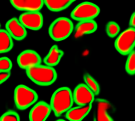

Second, we test our method on the BCD dataset.The manually labeled training set consists of five 1000*1000 images. Instead of training the models from random initialization, we use the training data to fine-tune the network model trained on the MOD dataset. Thus the model would adjust to a new dataset with much shorter time by training on a limited training set for a small number of epochs. In this experiment, only 2000 patches are extracted to fine-tune the pre-trained model. It takes about 10 seconds to train one epoch and the training is terminated after 70 epochs. Figure 9 shows the visual comparison between our algorithm and algorithm in [9] in terms of segmentation results. At last, we follow the same strategy in [21] to validate our method. The strategy is called leave-one-patient-out cross-validation. That is every time we train the model on 6 patient and use the rest one for validation. Table II shows that our method outperforms the state-of-the-art breast cancer nuclei segmentation method by a large margin in terms of precision, recall and F1 score.

Figure 9: Nuclei segmentation result over the BCD dataset. (a) two breast cancer image samples. (b) automatic segmentation result of [9]. (c) result of our method.